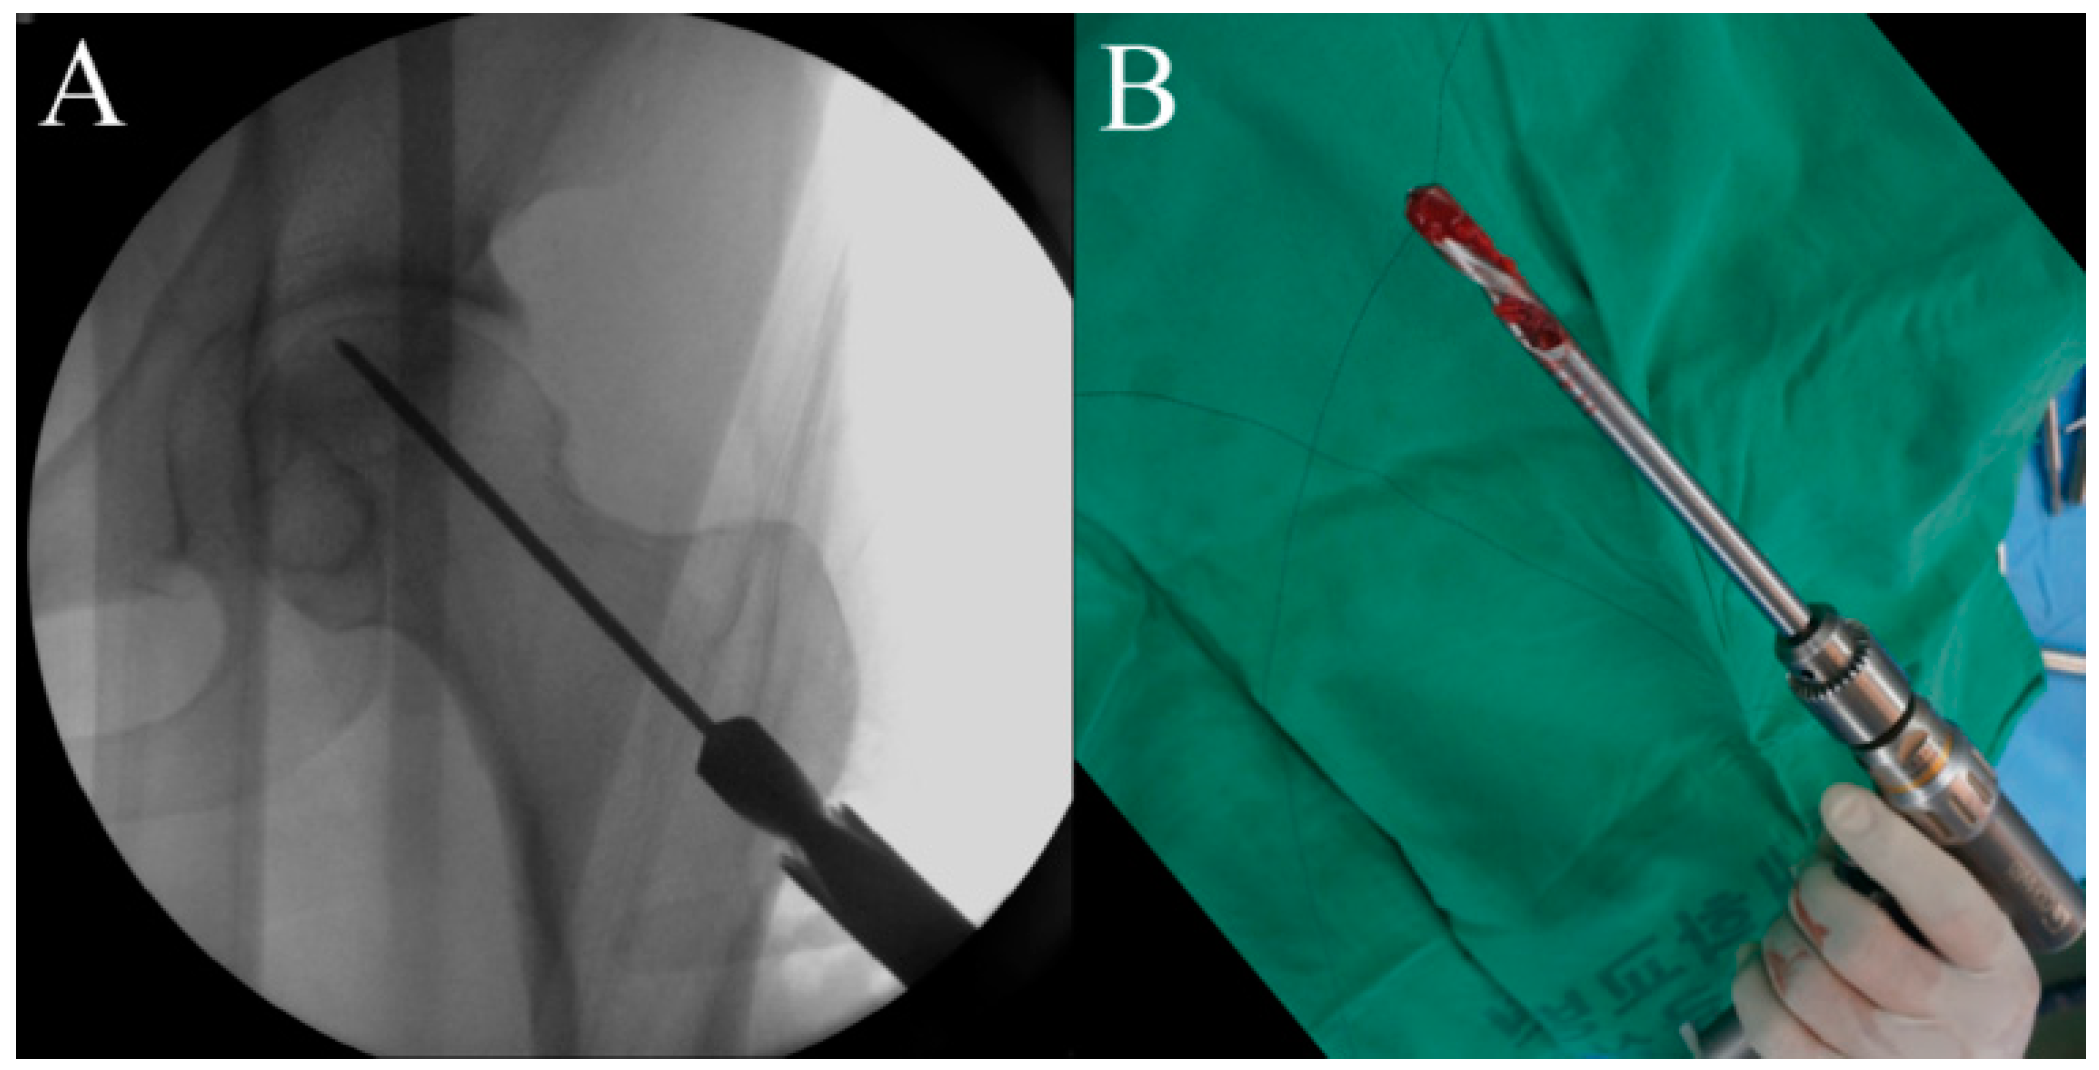

2.5. Procedure